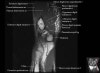

- Axial section

Axial T1 evaluates the tendons of the wrist and carpal tunnel, including the flexor retinaculum.

Axial PD fat suppressed evaluates the tendons of the wrist and carpal tunnel, including the median nerve.